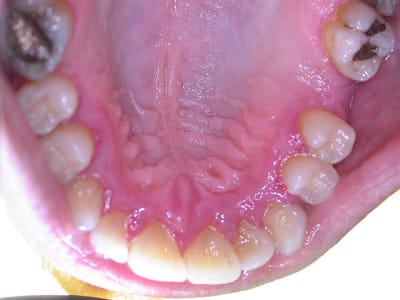

examen buccal .........voir les photos ........après ........ca vient

Bon controle de plaque, pas de tartre ni de colorations, inflammation en palatin seulement...